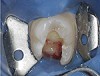

Fig. 6 A small access opening was prepared and canals explored.

Figure 6

Fig. 7 This conservative size preparation was enough to explore and find the three main canal orifices to the root canals.

Figure 7

Fig. 8 The MB2 canal, however, was not discovered until the preparation was widened to a rhomboidal shape, and the mesial dentinal shelf hiding the MB2 was removed with the aid of a bur and ultrasonic handpiece.

Figure 8

Fig. 9 The MB2 canal orifice was then exposed and a file was used to reach working length.

Figure 9

Fig. 10 This hidden MB2 canal had a separate apical exit that was prepared only after its discovery through enlarging the access opening.

Figure 10